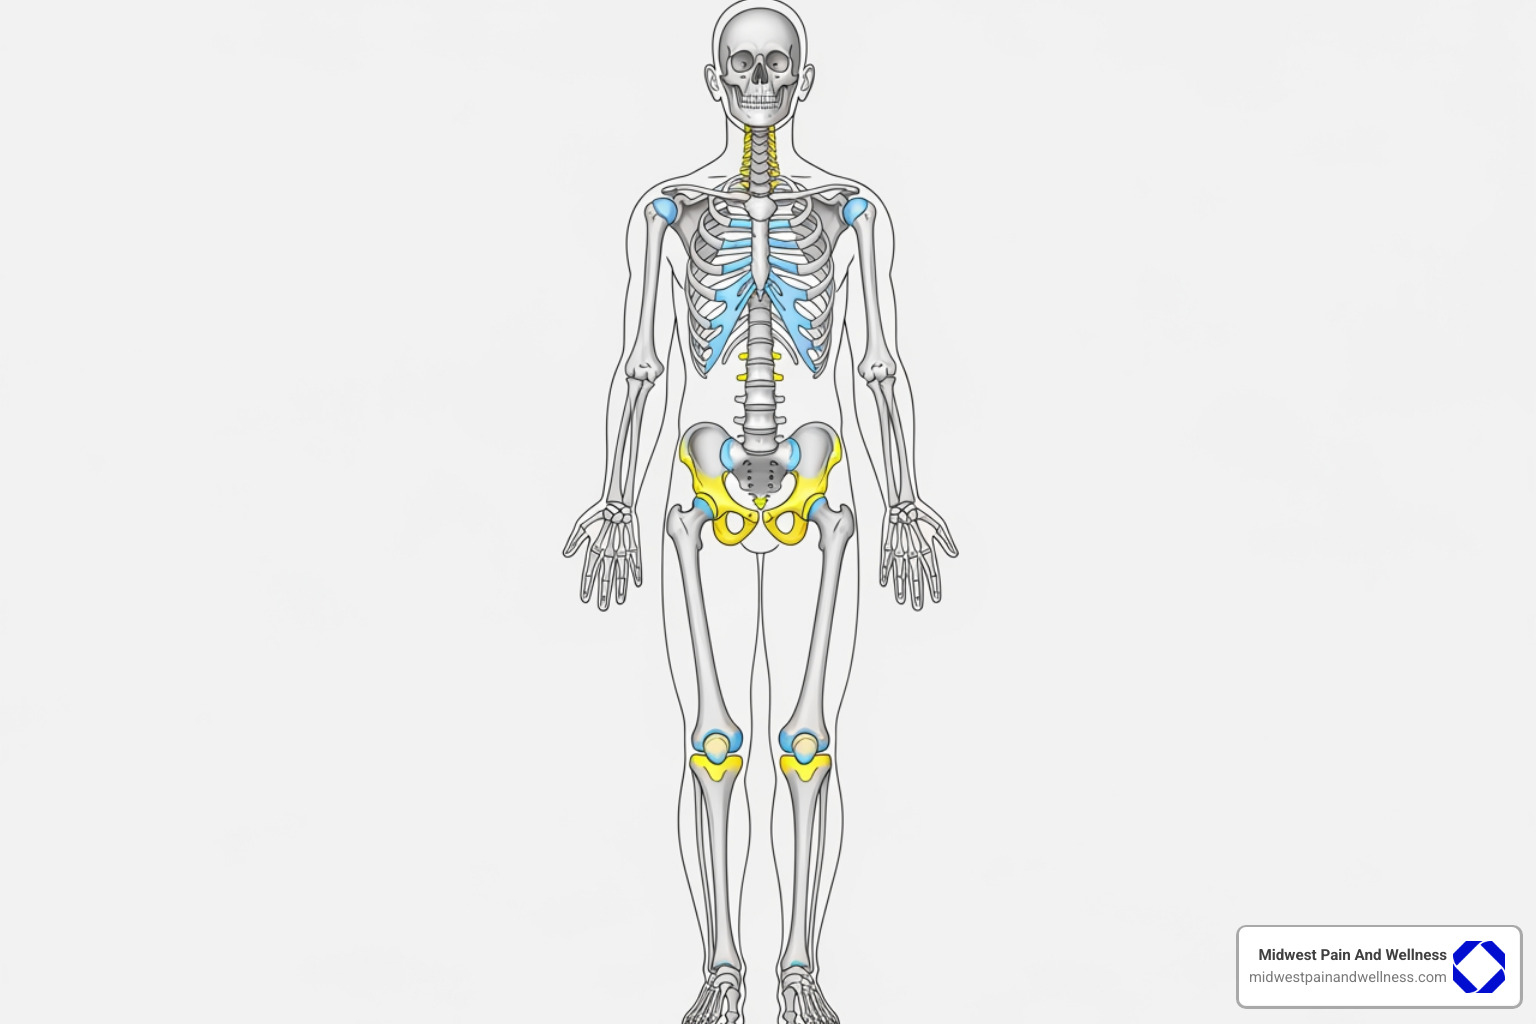

Conditions Treated with Pain Injections in Chicago

Pain injections in Chicago are incredibly versatile, offering hope for a wide range of acute and chronic conditions. Our approach is to create a personalized treatment plan that zeroes in on the specific cause of your pain.

Spinal, Back, and Neck Pain

These are among the most common reasons people seek pain management. We offer a variety of injections to precisely target the parts of your spine causing discomfort:

Joint and Extremity Pain

Targeted injections can also bring relief to other joints and extremities, making simple movements less painful:

- Arthritis: For arthritis in the Knees, Hips, or Shoulders, injections deliver anti-inflammatory medicine directly into the joint space to ease pain and improve movement.